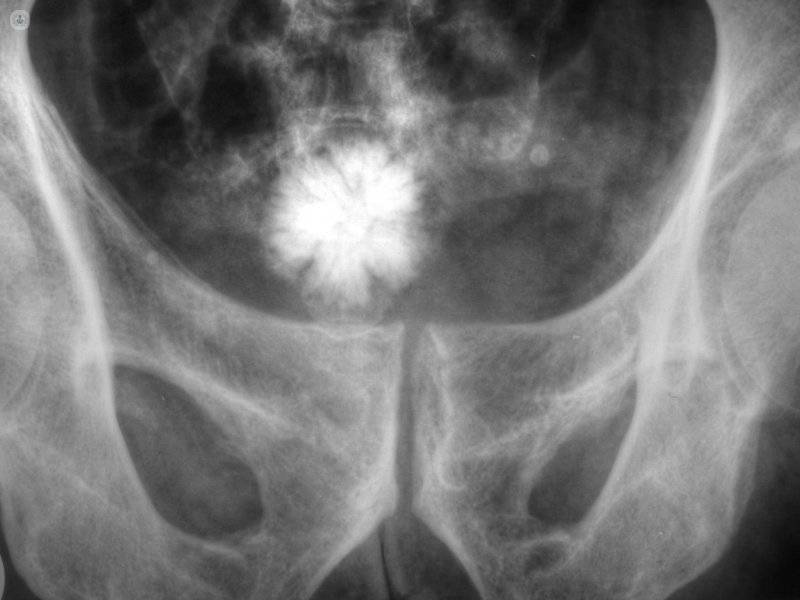

Frecuentemente, las litiasis no producen síntomas y se descubren de forma casual en una prueba radiológica (radiografía o ecografía). Ahora bien, cuando una piedra obstruye la vía urinaria, entonces el paciente siente dolor.

- Litotricia extracorpórea: procedimiento que consiste en la aplicación de ondas de choque (ondas de presión) en el punto más cercano a la piel de la litiasis. Estas ondas atraviesan los tejidos hasta llegar a la litiasis y la fragmentan, sin necesidad de cirugía. En principio, los fragmentos se eliminan posteriormente por la orina. No se recomienda a pacientes con litiasis de gran tamaño, ya que se generaría una gran cantidad de fragmentos y por tanto serian difíciles de expulsar y seguramente requeriría varias sesiones, que pueden prolongarse durante meses.